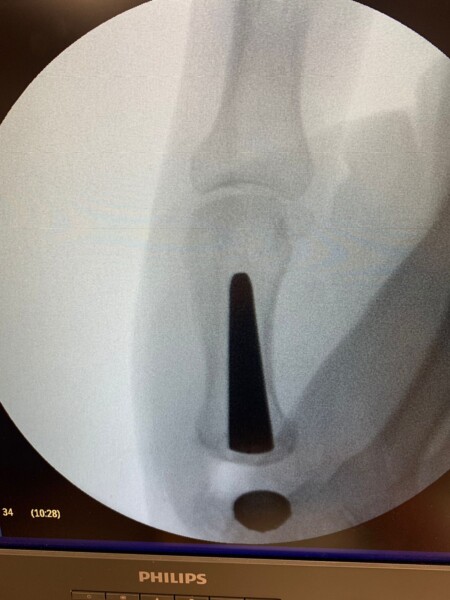

Dr. Juarez Cesca: La cirugía básicamente consiste en reemplazar la articulación de la base del pulgar, que es la articulación carpo metacarpiana del pulgar, por una articulación nueva, que sería la prótesis. Para ello, sacamos parte de los huesos y reemplazamos con la prótesis. La prótesis es exactamente lo mismo, como para que se pueda describir, es como una prótesis de cadera pero en el pulgar, hasta la forma es prácticamente la misma, nada más que otro tamaño y va en la base del pulgar.

Dr. Juarez Cesca: El material que tiene la prótesis es titanio y tiene un componente de hidroxiapatita que lo fija al hueso, es titano e hidroxiapatita, no lleva cemento para adherirse a la superficie. Todo esto de la hidroxiapatita hace que se vuelva rugosa la estructura, se fije y se asocie al hueso.